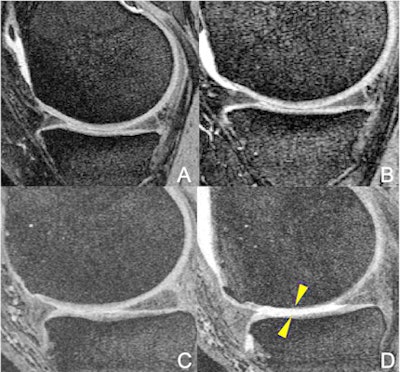

Schirò and colleagues used MRI to evaluate the rate of degeneration of the knee joint in 415 overweight or obese patients also enrolled in the U.S. National Institutes of Health's Osteoarthritis Initiative, which studies those with mild to moderate osteoarthritis.

The patients kept records of participation in six types of physical activity: ball sports, bicycling, jogging/running, elliptical trainer, racket sports, and swimming. Each person underwent a baseline MRI scan and a follow-up exam four years later. The investigators assessed any changes in the patients' knees using the Whole-Organ Magnetic Resonance Imaging Score.

Racket sports increased knee joint denigration much more than, for example, using an elliptical trainer; overall score also increased significantly more in the racket sports group compared with the jogging/running group. Those study participants who also played racket sports had significantly greater degeneration in the medial tibial cartilage compartment, where arthritis typically begins to appear.